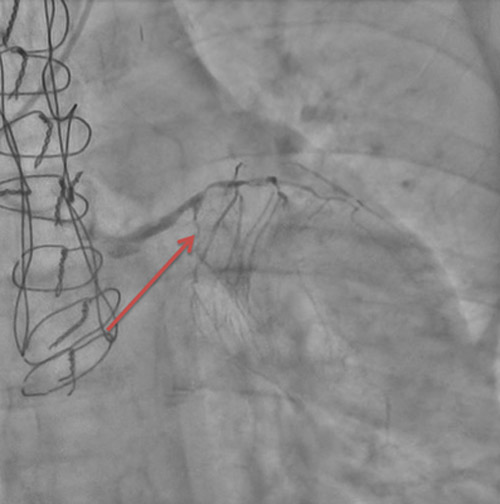

En effet, sur la coronarographie initiale, le réseau natif est quasi occlus, avec une subocclusion longue de l’IVA proximale donnant les premières branches septales, une occlusion chronique de la 2e diagonale, une occlusion chronique de la Cx proximale et de la CD ostiale.

Le montage en Y tout artériel vascularise le territoire latéral via la marginale, le territoire antéro-septo-apical via l’IVA et le territoire inférieur via l’IVP.

Image 3 : Occlusion chronique de la coronaire droite ostiale

Image 4 :Flèche 1 : anastomose mammaire interne gauche – IVA

Flèche 2 : Mammaire interne droite « branchée en Y » sur mammaire interne gauche

Flèche 3 : anastomose mammaire interne droite – Marginale

Flèche 4 : anastomose mammaire interne droite - IVP